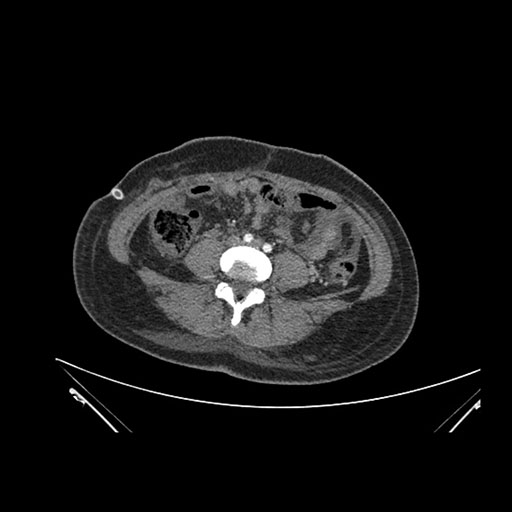

Axial Arterial

Imaging analysis

Based on initial findings, which issue(s) would you be most concerned about?